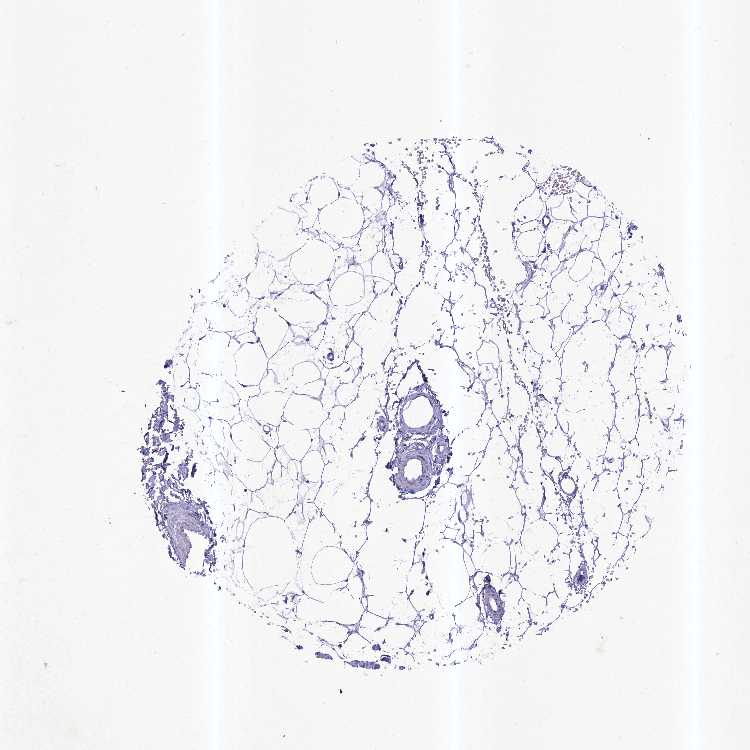

SOFT TISSUE 1 - Antibody stainingi

Antibody staining in the annotated cell types in the current human tissue is reported as not detected, low, medium, or high, based on conventional immunohistochemistry profiling in selected tissues. This score is based on the combination of the staining intensity and fraction of stained cells.

Each image is clickable and will lead to virtual microscopy that enables deeper exploration of all samples and also displays staining intensity scores, fraction scores and subcellular localization as well as patient and tissue information for each sample.

Antibody HPA043336

Chondrocytes Not detected

Fibroblasts Not detected

SOFT TISSUE 2 - Antibody stainingi

Peripheral nerve Not detected